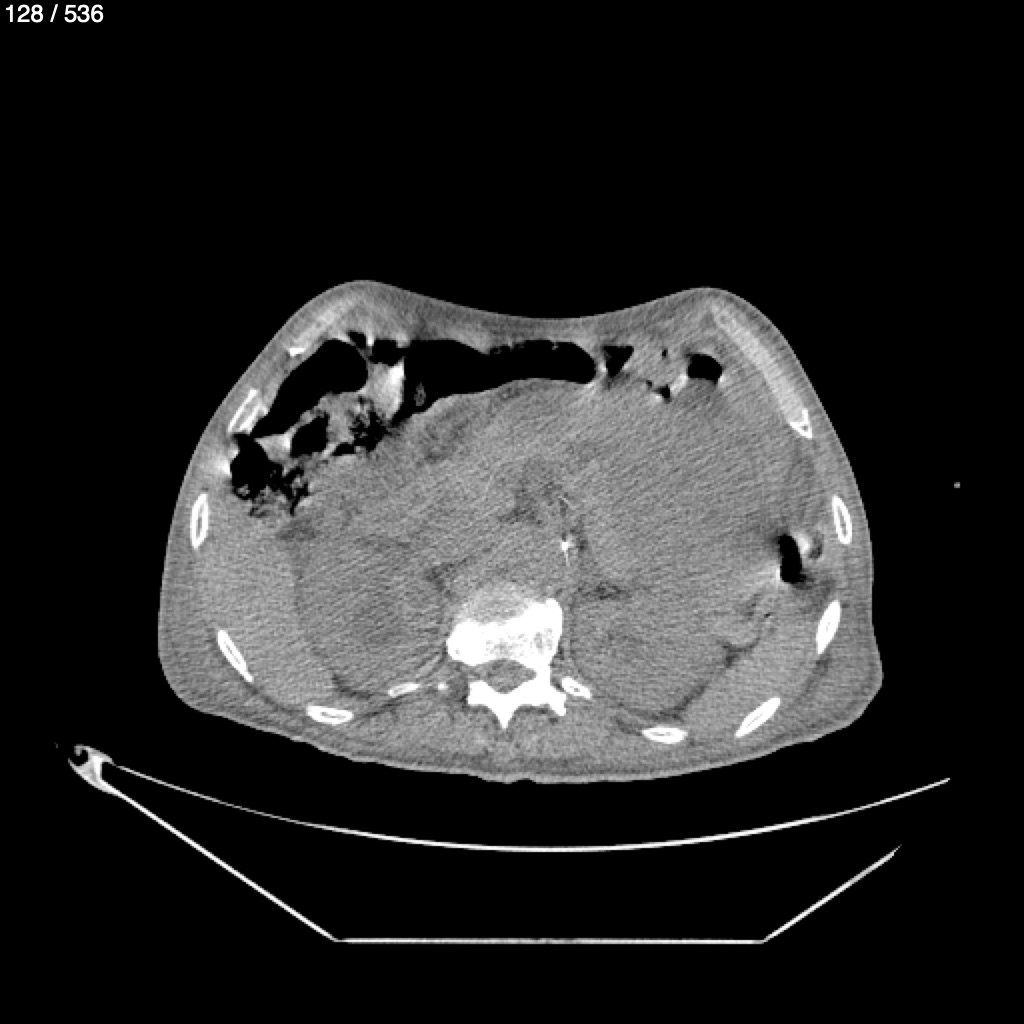

Angel Villalobos Palomeque 73 A - T.C Abdomen Simple